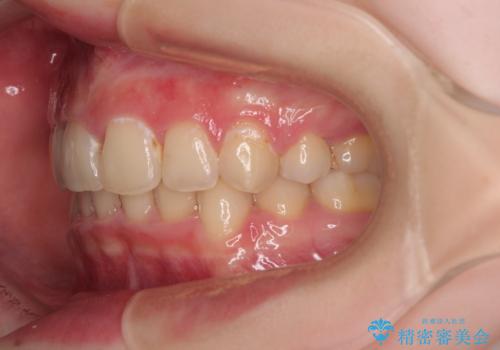

- デコボコになっている前歯を気にして来院された患者様です。

口元の突出感は気になっていないものの、デコボコを解消すると口元が前方に突出する可能性があるため、上下左右の第一小臼歯4本を抜歯して、ワイヤー装置にて矯正治療を行うこととしました。

下の前歯が隠れてしまうほど深く咬みこんでいたため、上顎前歯が前方に突出しているような印象がありましたが、咬み合わせが改善され、整った口元に仕上げることができました。